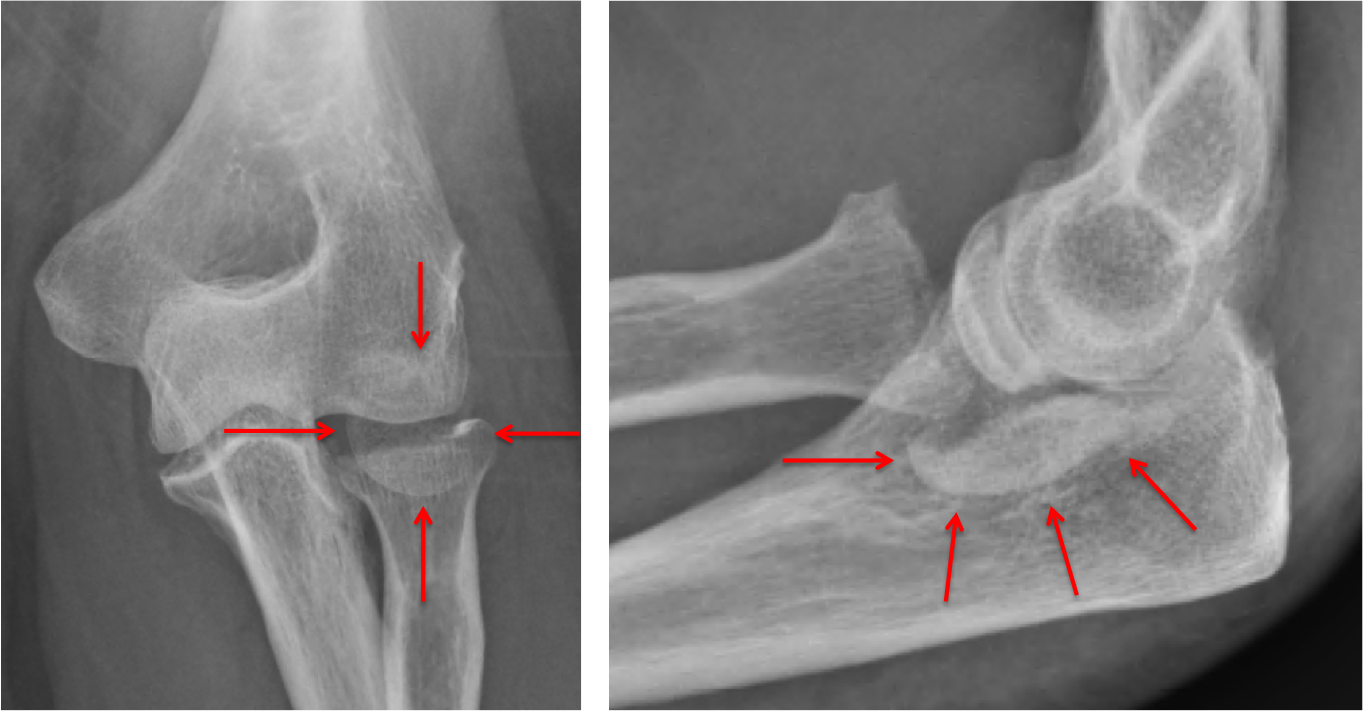

A radial head fracture is a break to the radius bone in the forearm just below the elbow joint and usually what is a radial head fracture?

Rehabilitation is begun as soon as possible after hip fracture surgery, often within a day. Here are some examples of exercises for you to try. Radial head fractures are more frequent in women than in men, and are more likely to happen in people who are between 30 and 40 years of age. Do not treat simple radial head fractures with prolonged immobilization. Joint motion is difficult to recover even with extensive physical therapy. Inpatient rehabilitation unit with 30 beds admitted by consult services from baylor st. The head of the radius articulates with the capitulum of the humerus. Luke's medical center and ben taub hospital. It tends to be more common in paediatric and elderly populations. Radial head fractures account for nearly 20 percent of elbow injuries, according to the american academy of orthopaedic surgeons. The force from a fall can be so great that it travels up to your arm and results in. Small fragments of broken bone may. If you have suffered a fractured radial head, find out more about your injury, and about what physio.co.uk can do what is a fracture of the radial head? Regardless of the type of fracture or the treatment used, exercises to restore movement and strength will be needed before resuming full activities. The radius is the one of two bones in the forearm. In children, it occurs more often in males whereas it is more common in females in the older population. Radial fractures frequently occur as the result of trying to break a fall using your hands.